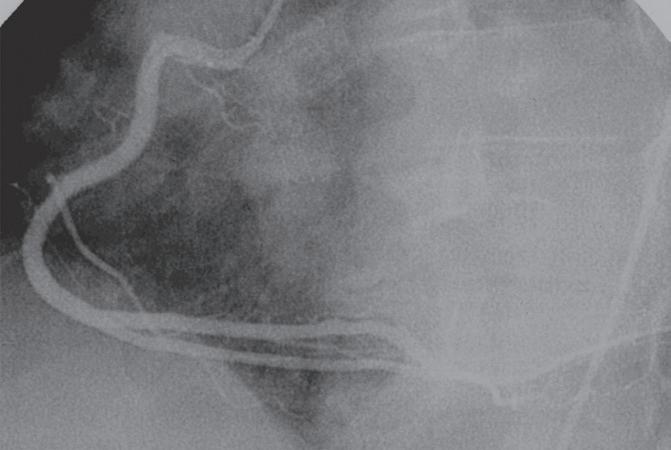

Figura 18.36 – Angiografia da artéria coronária direita. Visualização das diversas colaterais. A. Oblíqua anterior esquerda 45º caudal 15º; B. Oblíqua anterior direita 45º.

Figura 18.37 – Coronariografia da artéria coronária direita (dominante).